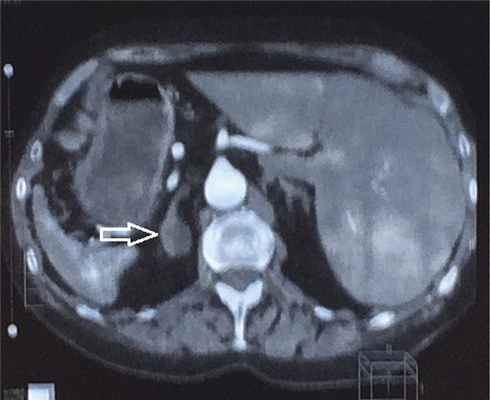

Эзофагогастродуодено- и колоноскопия, мультиспиральная компьютерная томография (МСКТ) грудной клетки объемного образования не выявили. При МСКТ брюшной полости и забрюшинного пространства (выполненной до нейрохирургического вмешательства) были обнаружены два овоидных образования левого надпочечника с четкими и ровными контурами; одно — размером 1,8×2,3×2,5 см и плотностью 19Н, второе — 2,0×2,3×2,5 см и 3Н (рис. 1), которые в связи с результатами БДП и селективного забора крови из нижних каменистых синусов были расценены как вторичные аденомы при БИК.

Рис. 1. МСКТ органов брюшной полости и забрюшинного пространства. Стрелкой указано объемное образование левого надпочечника.